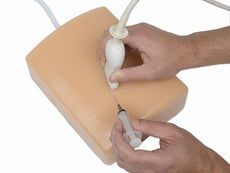

Replacement tissue insert for the Thoracentesis and Thoracostomy Ultrasound Training Model (BPTT1000-1).Choose from three options:

- Tissue Insert

- Anterior Portal Insert

- Lateral Portal Insert